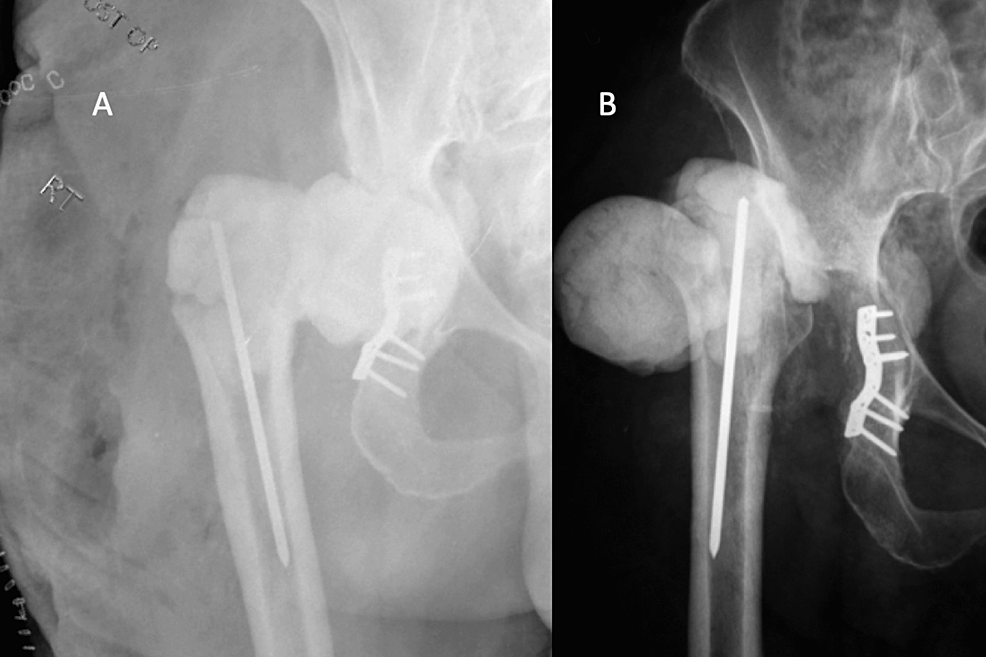

From www.researchgate.net

Anteroposterior radiographs of the hip spacer A) without cementation What Is A Temporary Hip Spacer This spacer is treated with antibiotics to. in the first surgery, your doctor will remove the implants and place a temporary cement spacer in your hip. there are several different types of spacer: the rehabilitation program following hip spacer implantation emphasizes early, controlled functional range of motion to. — i have undergone 5 hip replacements and. What Is A Temporary Hip Spacer.